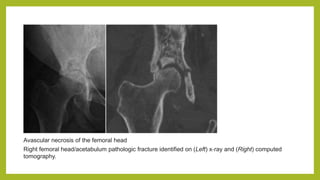

Avascular necrosis of the femoral head

Right femoral head/acetabulum pathologic fracture identified on (Left) x‐ray and (Right) computed

tomography.